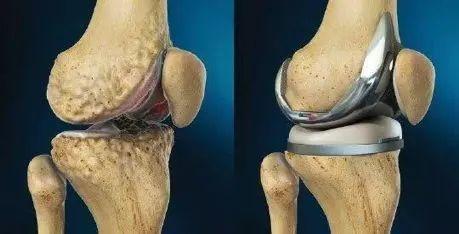

在臨床中,總有一部分患者對于上述的保守治療效果都不理想,這個時候,我們就需要通過手術來幫助他們解決問題。對于晚期的嚴重的膝關節骨關節炎而言,我們通常需要實行人工全膝關節置換術來幫助這些患者。

簡單的說,這一手術就是將病變嚴重的膝關節股骨一側和脛骨一側的軟骨和部分骨質以特殊的工具去除,然后根據每一個患者的膝關節尺寸選擇合適型號的假體,用一種叫做骨水泥的粘合劑固定在膝關節內。通過這種手術,患者可以很快的正常行走和進行日常生活工作。